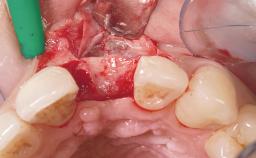

Immediate Placement of an Implant in a Maxillary Right Central Incisor Site

A 30-year-old female patient was referred to the office for the treatment of tooth 11. Her chief concern at the initial visit was to inquire, “Why is my tooth pink?” Upon clinical examination, it was determined that tooth 11 had a previous history of trauma and that the clinical crown had become noticeably pink in color as a result of internal resorption. This diagnosis was confirmed radiographically, indicating a large radiolucency involving the central and distal portions of the clinical crown. It was determined that restoration of this tooth was not possible, and that extraction was indicated. The presence of a mid-line diastema, which the patient wanted to reproduce, directed the treatment plan for tooth replacement utilizing a dental implant.

| Bone Augmentation | Horizontal|Simultaneous |

| Augmentation Materials | Autogenous chips|Membrane |